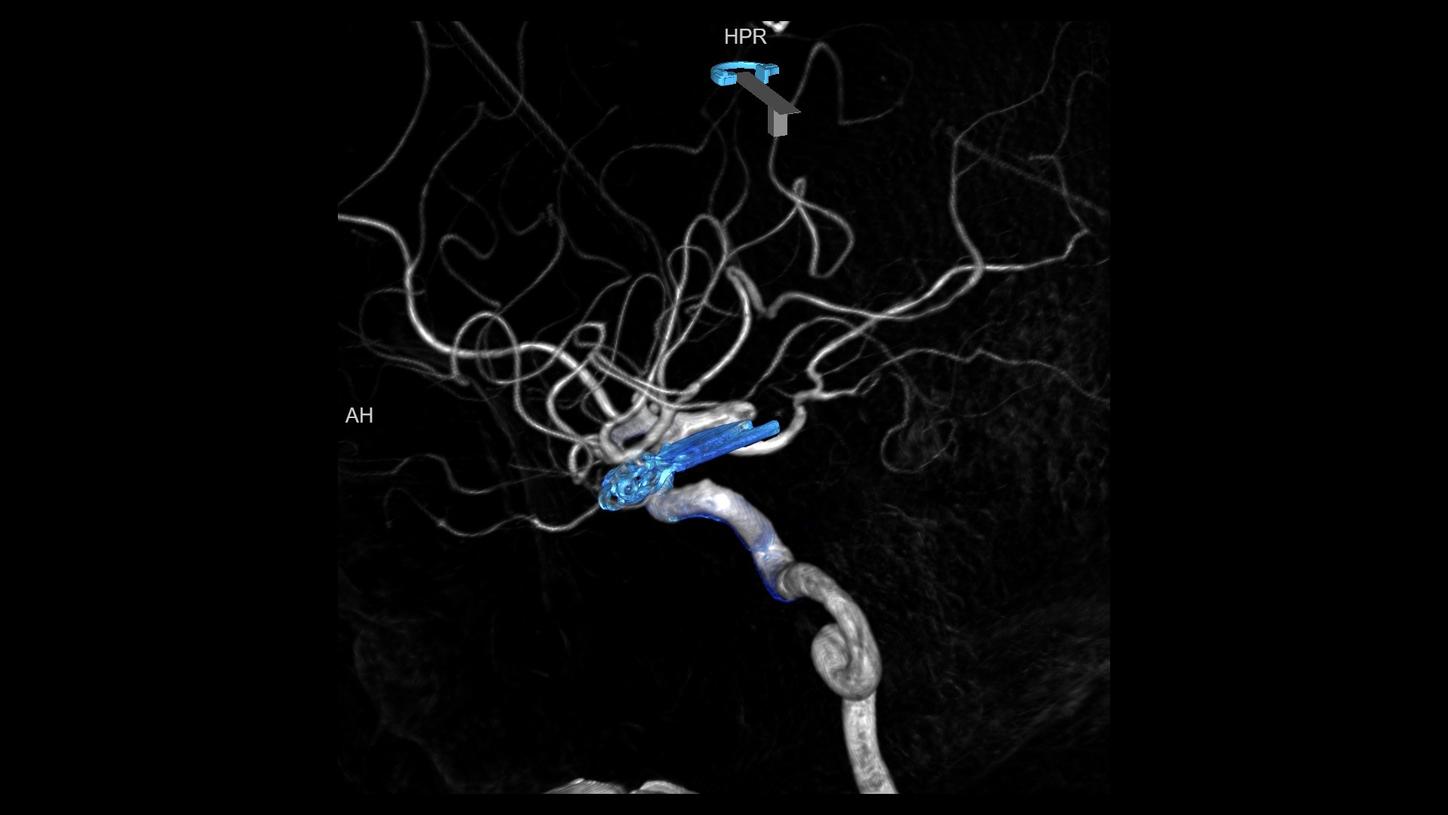

NeurologyDiscover our solutions for imaging and image guided therapy in Neurology

Neurological disorders can threaten the fundamental hope of a happy and independent life, spent with the people we care about. Helping patients achieve their highest potential independence by supporting your diagnosis and treatment is what we strive for.